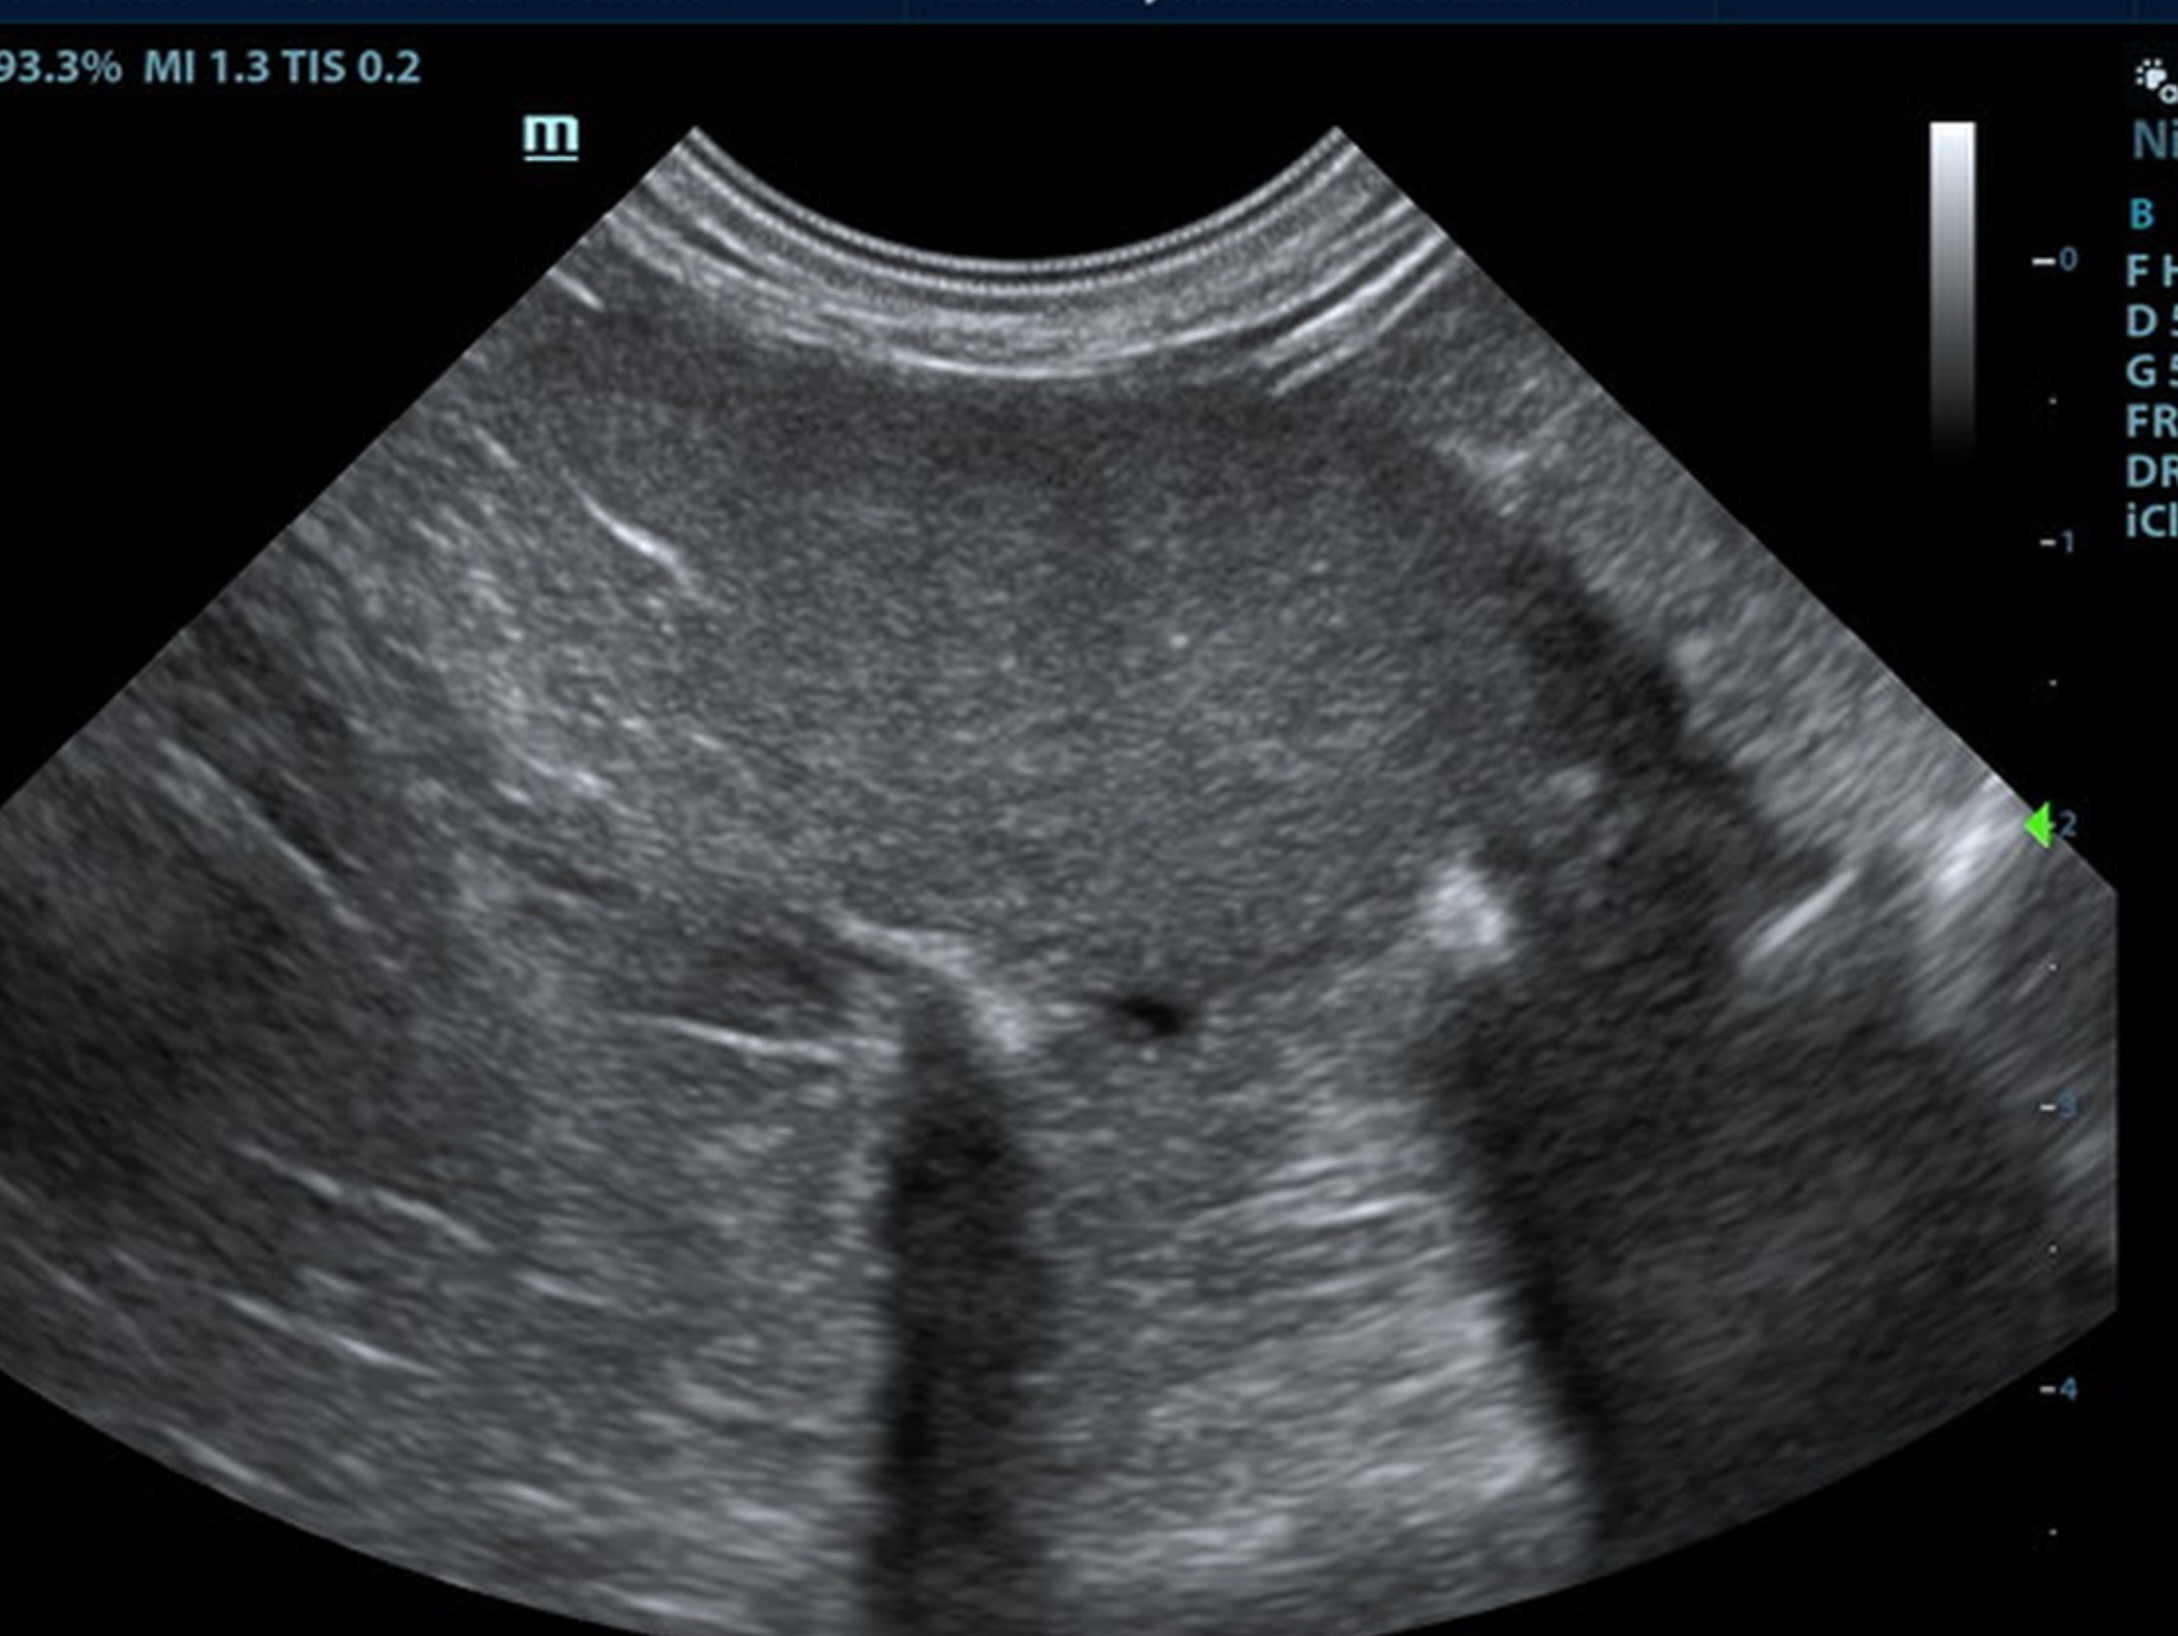

The spleen was mildly enlarged and folded upon itself caudally. The splenic parenchma was uniform. The spleen measured 0.84 cm.